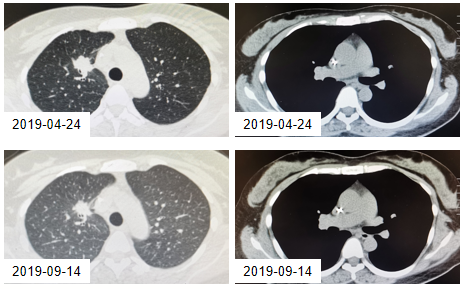

2019年11月18日,复查影像学结果提示:肺部原发病灶较前增大,肝脏出现新发病灶。

图3. 9月14日与11月18日的CT检查结果

2019年11月27日,患者接受奥希替尼二线治疗,在治疗过程中,肺部原发病灶略缩小、肝脏转移病灶持续稳定。

图4. 2019年11月18日与2020年4月14日的CT检查结果